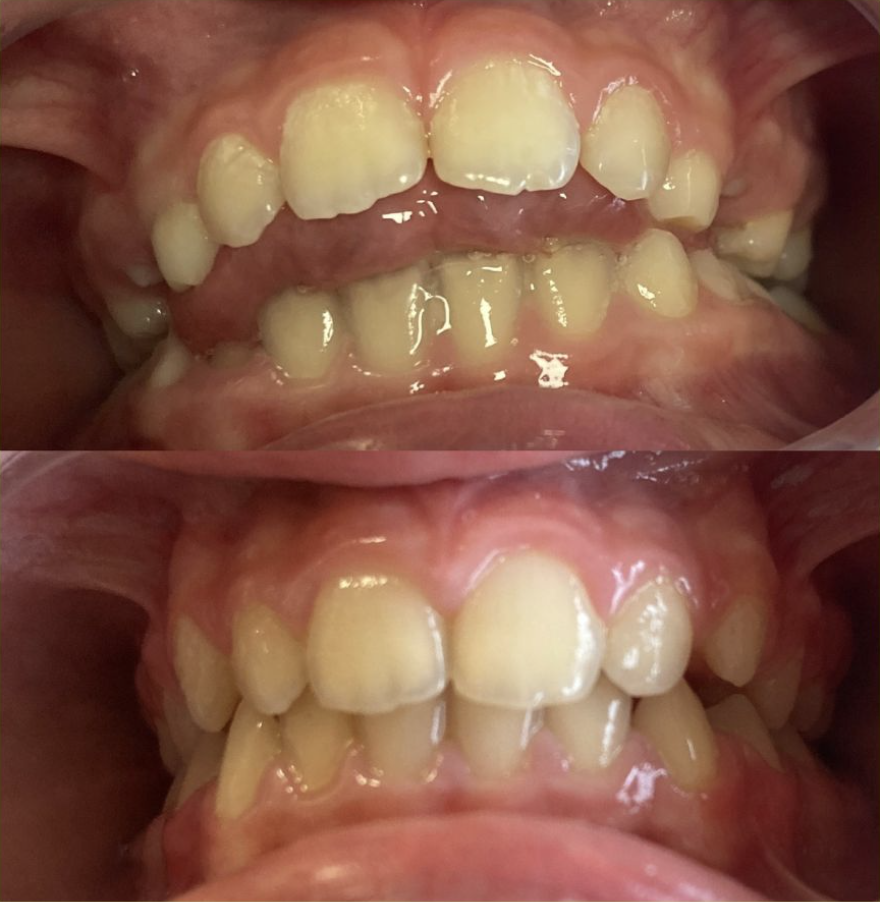

📸 Parfois, une image vaut mieux qu’un long discours…

Voir les photos avant/après sur Instagram : Instagram